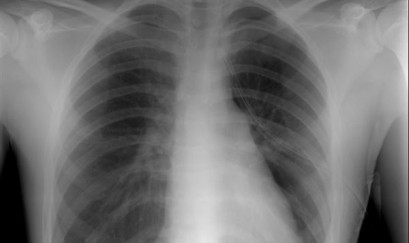

Phổi tắc nghẽn COPD

Điểm mặt các triệu chứng bệnh phổi tắc nghẽn mạn tính - COPD

Chế Độ Vận Động Hợp Lý: "Chìa Khóa" Giúp Người Bệnh COPD Hít Thở Dễ Dàng Hơn

7 lời khuyên cho bệnh nhân phổi tắc nghẽn mạn tính COPD

[NEW] Cảnh báo biến chứng Suy tim do phổi tắc nghẽn mạn tính COPD lâu năm

Chú ý tập luyện, tránh tái phát Đờm, Ho, Khó thở khi trời nồm ẩm

Cập nhật xu hướng điều trị COPD mới nhất - GOLD 2023

Vì sao bệnh phổi tắc nghẽn mạn tính COPD trong thời tiết giao mùa lại trở nặng?

Những thông tin về bệnh phổi tắc nghẽn mạn tính COPD giai đoạn 3 mà bạn không nên bỏ qua

[Giải đáp] Bệnh phổi tắc nghẽn mạn tính COPD giai đoạn 2 sống được bao lâu?

Chẩn đoán và điều trị bệnh phổi tắc nghẽn mạn tính COPD giai đoạn 1 như thế nào?